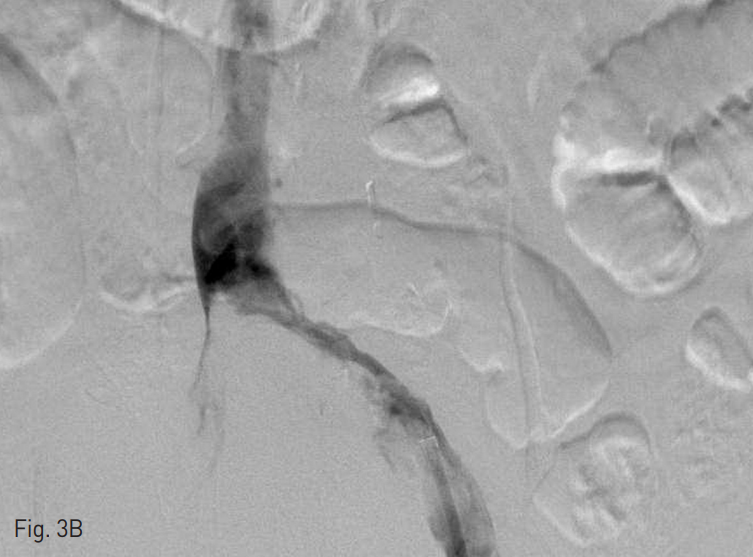

초음파 유도하에 오른쪽 총대퇴정맥을 천자하였고, 5 Fr cobra catheter (Cook, Bloomington, IN, USA)를 삽입하여 정맥조영술을 시행한 결과 혈전으로 폐색되어 있는 간하부 하대정맥과 양측 신정맥 내부의 혈전 및 다수의 측부 순환들이 관찰되었다 (Fig. 2). 왼쪽 총대퇴정맥에 11 Fr arrow long sheath (Johnson & Johnson Medical, New Brunswic, Canada)를 삽입하여 왼쪽 장골 정맥과 하대정맥 내에 있던 혈전을 흡인하였고, 6 Fr fogarty balloon catheter (Edward Lifesciences, Irvine, CA, USA)을 이용하여 왼쪽 장골 정맥에 유착되어 있던 혈전도 제거하였다 (Fig. 3). 왼쪽 장골 정맥과 하대정맥 내에 잔재하는 혈전에 대해서는 MCIS thrombolysis catheter (Cook, Bloomington, IN, USA)를 삽입하여 밤 사이 12시간 동안 시간당 80,000 unit의 속도로 urokinase를 투여해서 혈전 용해술을 시행하였으며, 동시에 양측 총대퇴정맥 sheath를 통하여 heparin을 시간당 150 unit을 각각 투여하였다. 간내부 하대정맥의 혈전으로 인해 하대정맥 필터 삽입술은 시행하지 않았다.

Fig. 3

A. Left iliac vein thrombus was removed using 6 Fr fogarty balloon catheter.

B. Aspiration thrombectomy was also done in left iliac vein.